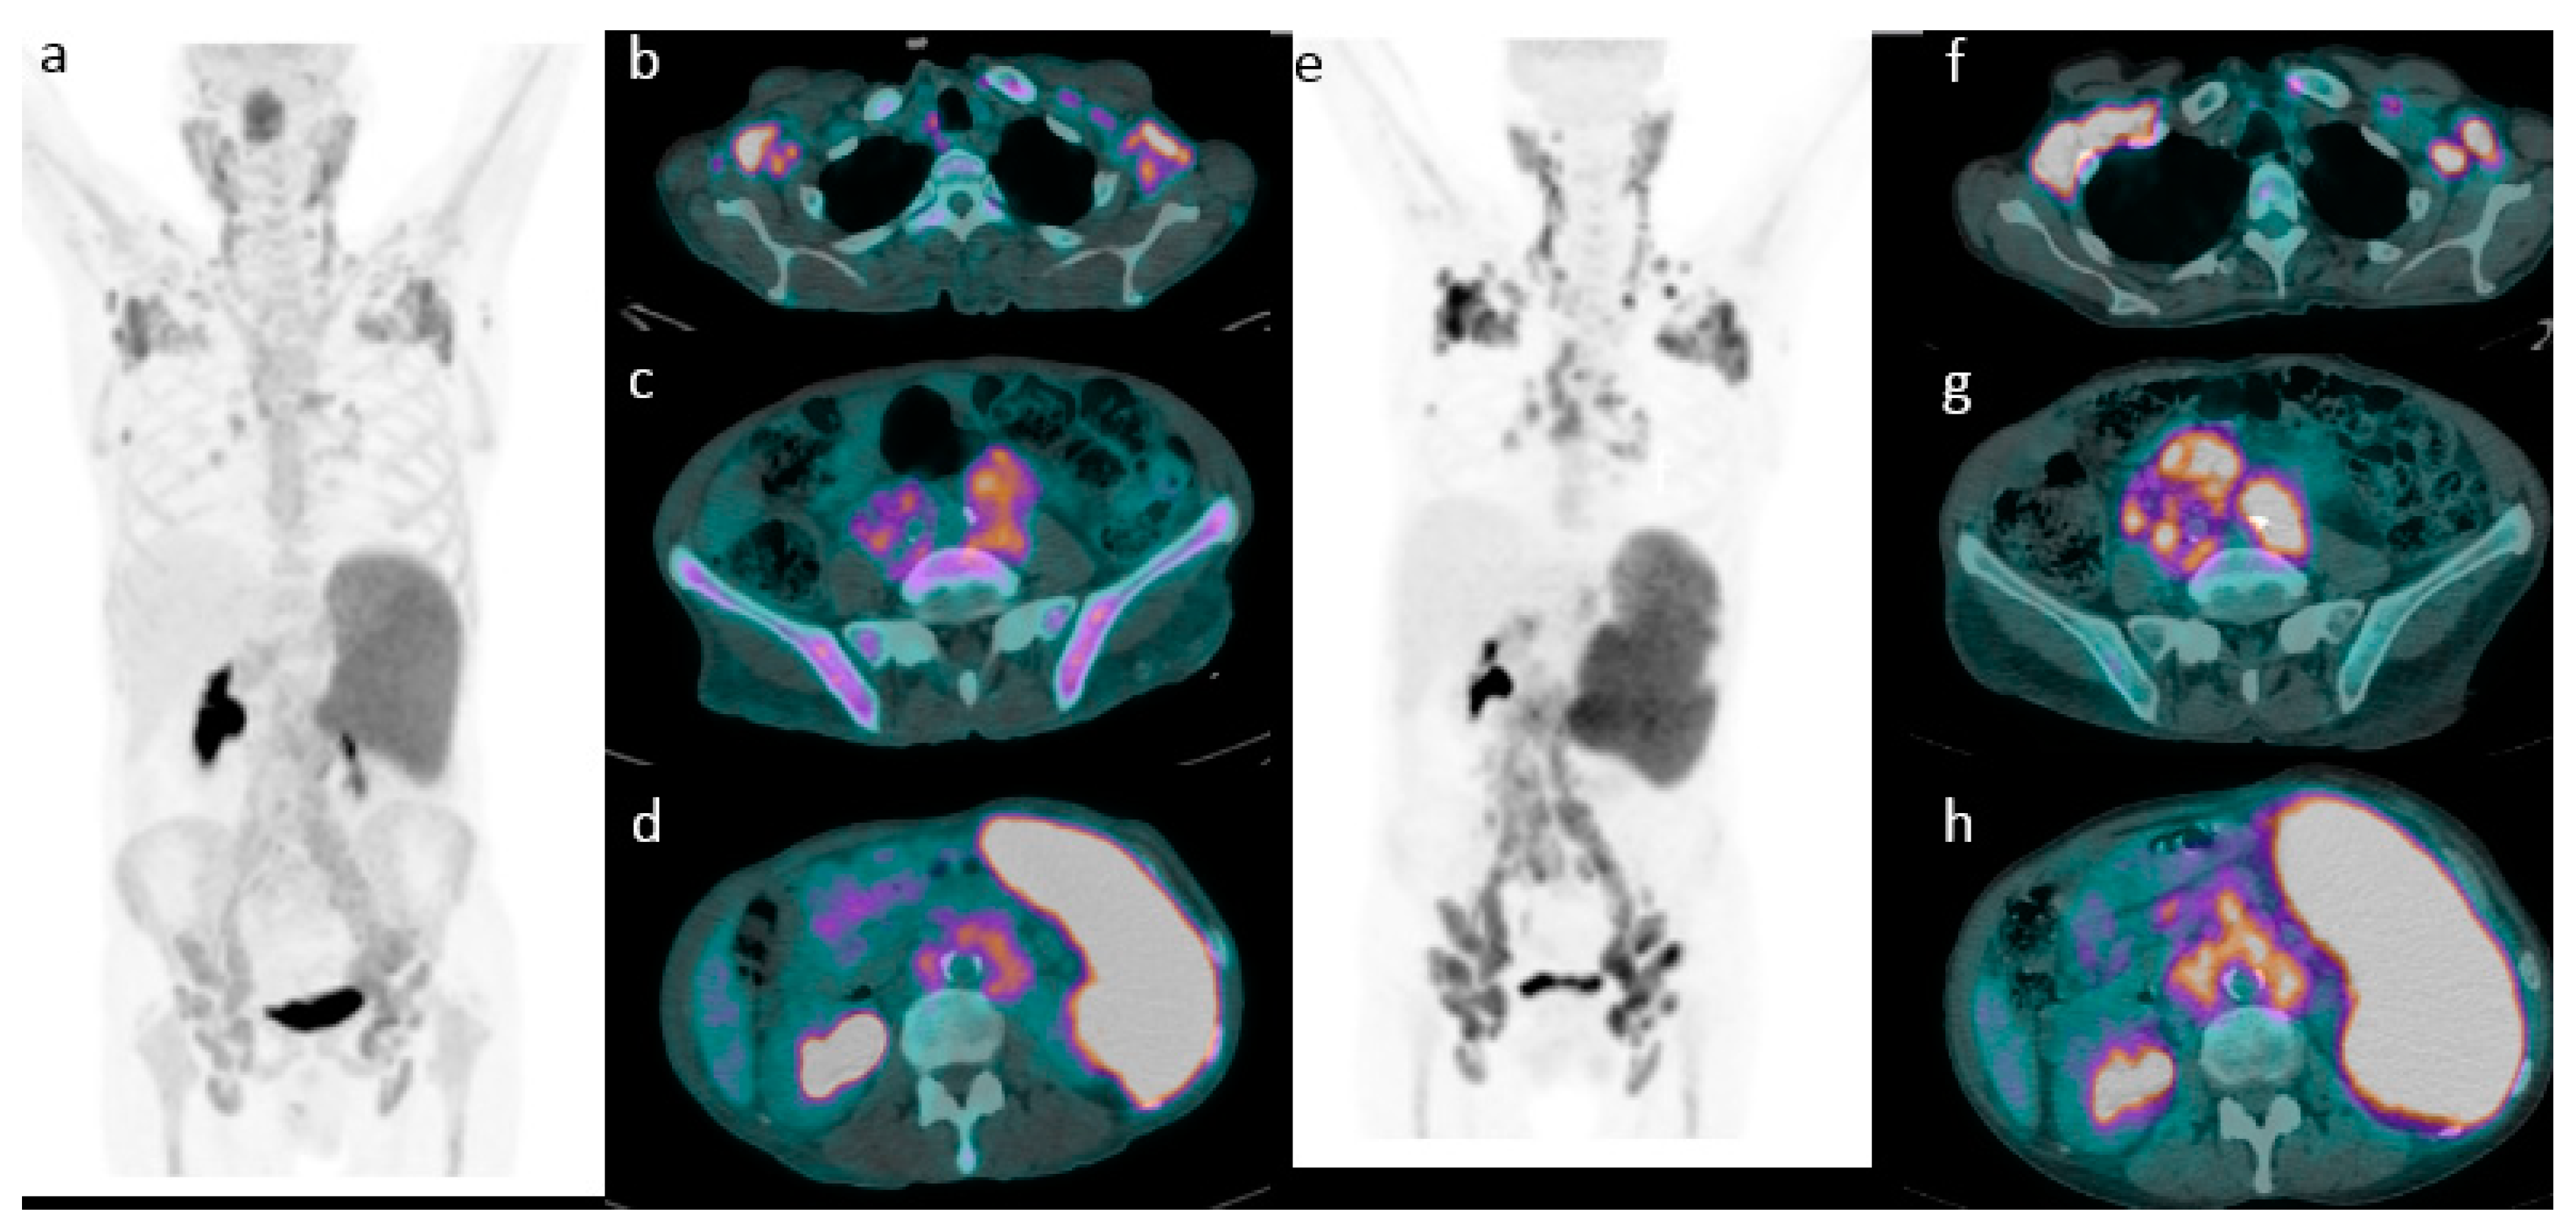

2.2. 18F-FDG PET/CT Evaluation for Initial Staging

Application of Deauville Criteria